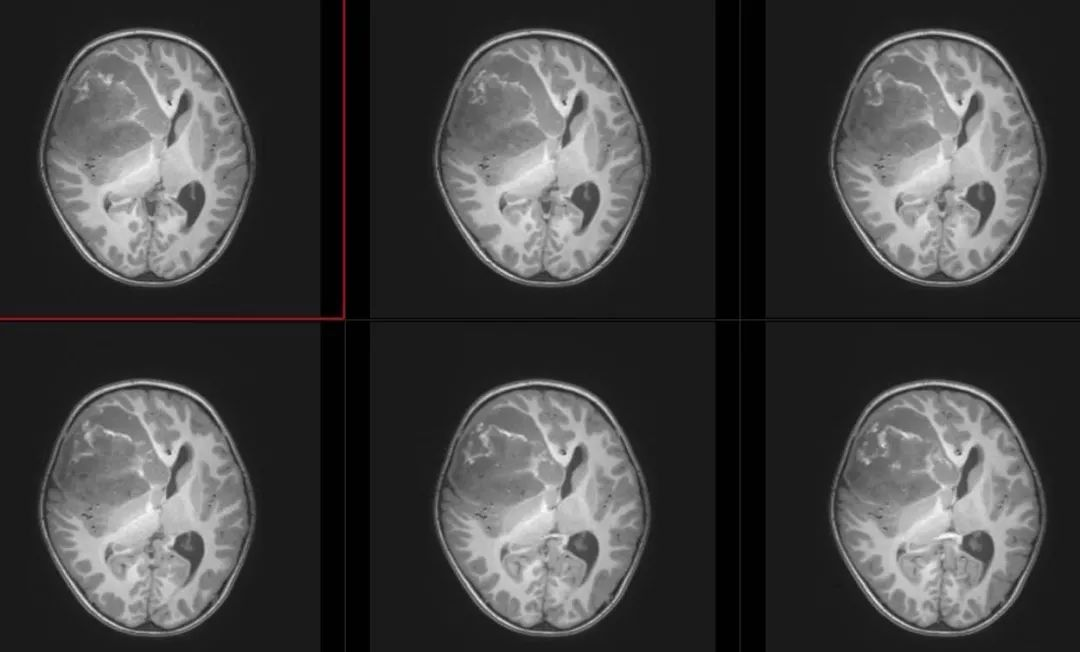

术前T1轴位

术前T1冠状位